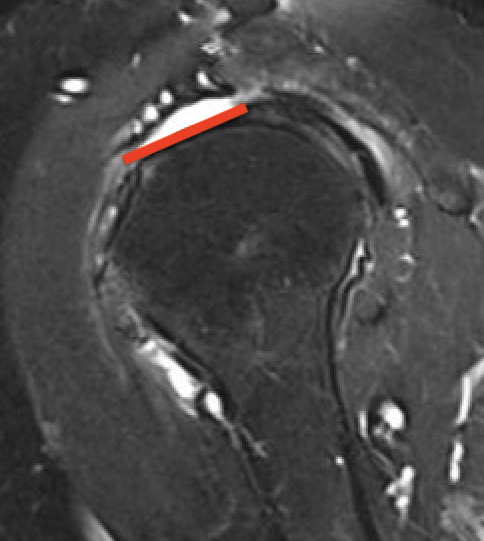

Small full thickness rotator cuff tear of supraspinatus - retracted to footprint

Large full thickness tear of supraspinatus and infraspinatus tendon - retracted to midhumeral head

Massive rotator cuff tear of the supraspinatus and infraspinatus tendon - retracted to glenoid

Tangent sign

- sagittal MRI

- line connecting superior coracoid and superior border scapular spine

- if supraspinatus muscle is below line, there is significant atrophy

- positive tangent sign / significant atrophy associated with larger tears / irrepairable tears

Negative tangent / no atrophy Positive tangent / significant supraspinatus atrophy